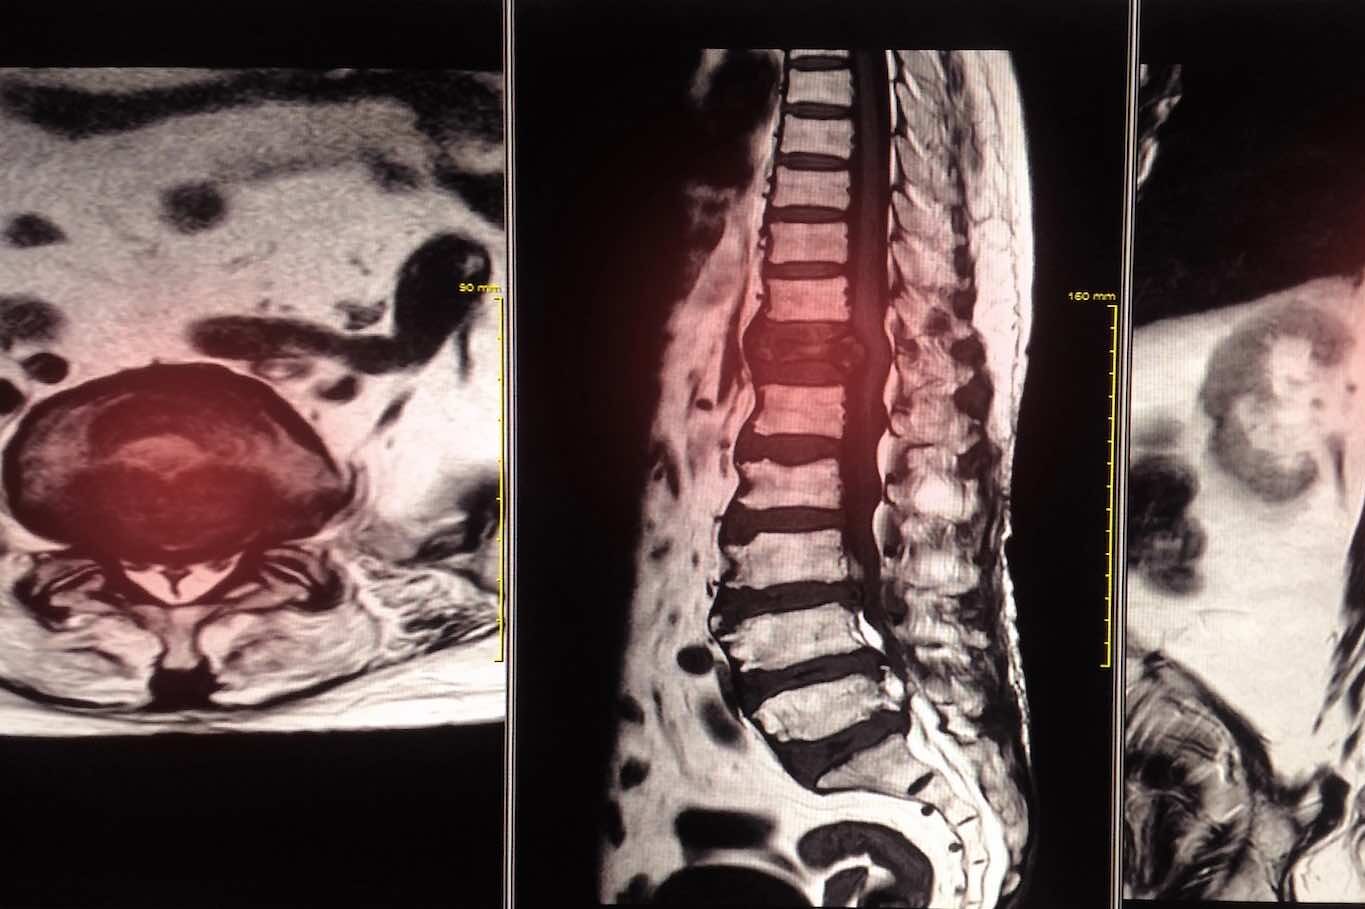

Schilddrüsensonographie

Abdominalsonographie (Bauchorgane)

Lungensonographie

Die drei Säulen unserer Praxis – Präventions-Diagnostik, Spezialsprechstunden und Kardiovaskuläre Leistungsanalyse – sind eng miteinander verzahnt, um dieses Ziel zu erreichen. Durch die detaillierte Diagnostik, die bis zur Kardiovaskulären Schlafmedizin reicht, erkennen wir komplexe Zusammenhänge, die andernorts oft übersehen werden. Beispielsweise legen wir einen besonderen Fokus auf das Herz-Hirn-Gefäß-System: Risikofaktoren wie unbehandelter Bluthochdruck oder Herzrhythmusstörungen sind nicht nur für das Herz, sondern auch für die Gehirngesundheit und das Schlaganfallrisiko entscheidend. Mittels spezieller Gefäßuntersuchungen tragen wir aktiv dazu bei, diese Risiken frühzeitig zu entschärfen.